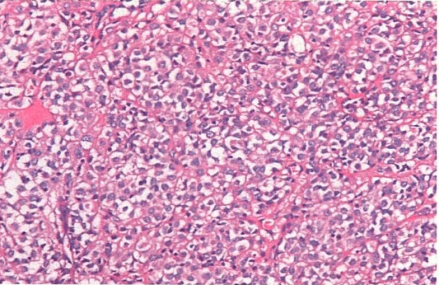

患者男,60岁。因“呕血3小时”急诊就医。胃镜检查,发现胃体后壁巨大隆起肿块,表面黏膜糜烂。肿块固定,边界尚清,大小约5.2cm×4.9cm。胃窦部黏膜高低不平部分呈颗粒状。胃镜活检标本组织学检查,显示病变由异型上皮样细胞组成,形态如图所示。

1.如果免疫组织化学检测CD117阳性,病理诊断是上皮样型胃肠道间质肿瘤。下列提示对靶向药物伊马替尼治疗有效的分子病理检查结果是